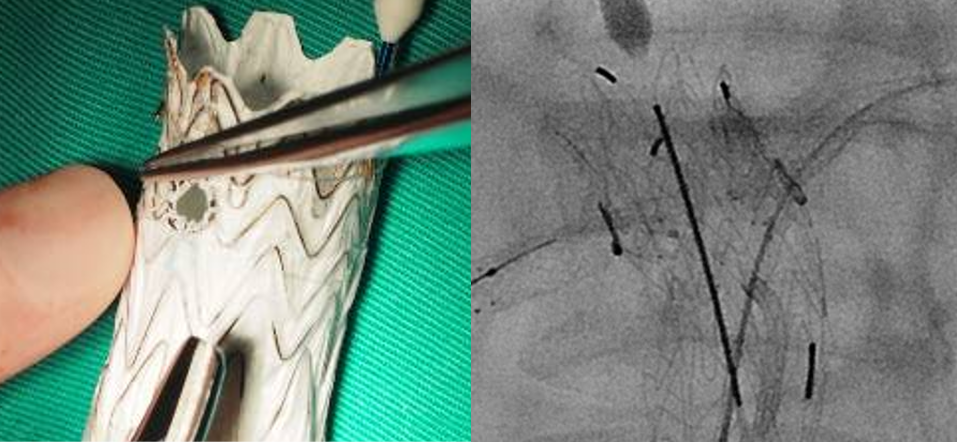

缝制分支和marker

分支

选择Viabahn而非人工血管(人工血管无自膨,容易压闭塞)

首选Gore的CV系列缝线

Marker

0.014导丝头端:显影好,但是不好缝制且贵

弹簧圈:显影好,好缝,但贵

显影条:显影尚可,非常便宜,可获得性强;同时还有一定的弹性密封作用,强烈推荐

导丝头端

显影条